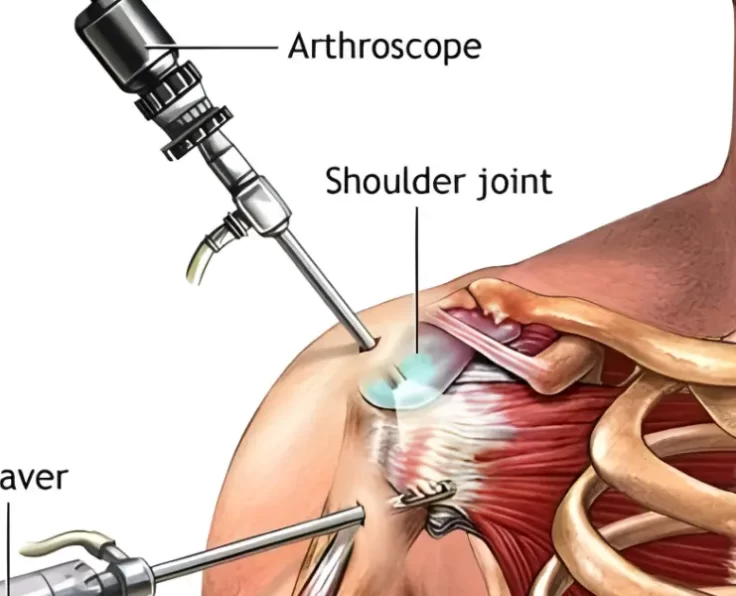

Shoulder Arthroscopy

Arthroscopy is a procedure used by orthopaedic surgeons to evaluate and treat joint conditions. A shoulder arthroscopy procedure is commonly performed to relieve pain and…